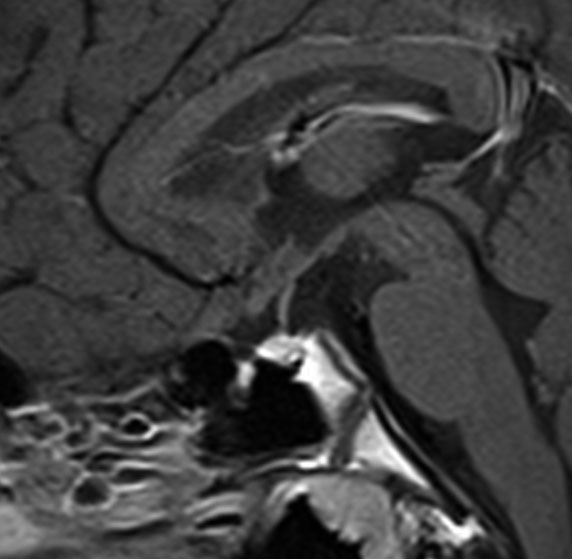

血清HCG-beta 4.5mIUで,下のMRIに見られるように第3脳室(視床下部)のグリオーマ(毛様細胞性星細胞腫)と見間違うような腫瘍でした。下垂体柄は太くなっていないし下垂体のサイズも普通です。もちろん水頭症もありませんので,開頭手術で生検をしてgerminomaの診断を得ました。

上のMRIで視神経交叉が腫大しているのが解りますが,下のMRI CISS画像では更に明らかです,左右の視神経と視交差と視索が腫大していました。視力を計ったら,右0.6,左1.5でいびつな視野欠損がありました。腫瘍はのう胞形成しながら左の視床下部から大脳基底核にも浸潤していました。